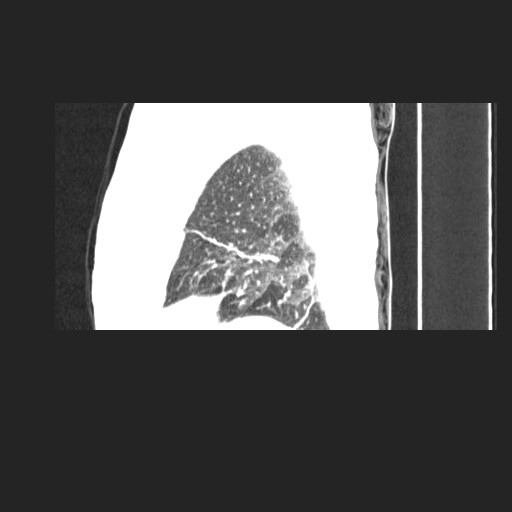

间质性肺炎,有纤维化趋势。

1)慢性支气管炎并肺部感染、肺气肿。2)肺间质纤维化。

间质性肺炎,左下肺机化性肺炎。